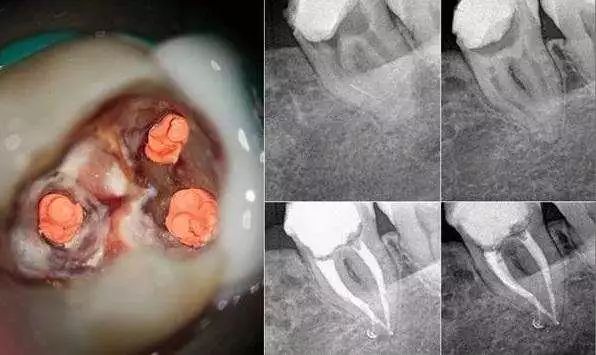

1、去除牙体的龋坏组织,并将牙髓腔暴露出来,用拔髓针将感染的牙髓拔出(这也是俗称的“抽牙神经”一词的来源)。

2、测量根管的长度。因为牙齿是不透明的,必须通过一些器械测量根管的长度,现在一般使用根管长度测量仪进行测量。

3、使用金属锉对根管的形状进行预备,也就是将根管管道上的脏东西磨除干净。随着技术的进步,已经从传统的手用器械进展到机械方法,一方面可以使根管预备的质量提高,另一方面也会使治疗时间缩短,让患者和医生的体验更好。

首先根管治疗是分牙位的,也就是说将全口牙齿分为3类:前牙、前磨牙(双尖牙)和磨牙这三类。前牙治疗因为简单所以价格也是最低的,前磨牙其次,磨牙因为牙根复杂并且操作不方便,所以价格最贵。

另外针对于磨牙来讲,通常磨牙会有3到4个牙根,但是牙根里面的神经可能会有多根,正常的磨牙根管治疗是指治疗3根神经的费用,如果这个牙齿的神经数量超过3根那么每多出来一根就要加收一根神经的费用。